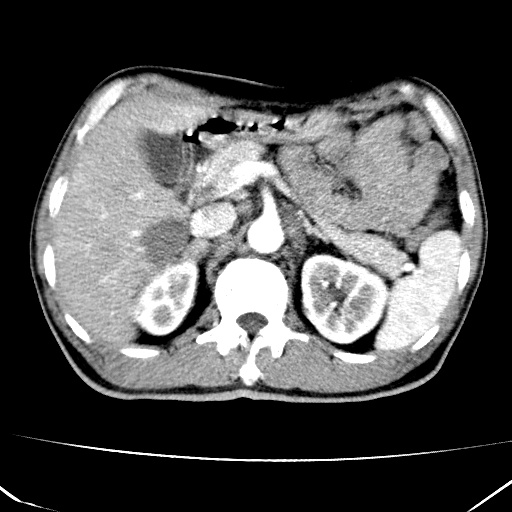

标题: CT17975:请求会诊。男、57岁。上腹部胀痛2天。临床诊断:糜 [打印本页]

标题: CT17975:请求会诊。男、57岁。上腹部胀痛2天。临床诊断:糜

肝脏多发类圆形低密度影,考虑肝脏转移瘤,肝胃韧带一淋巴结肿大,原发?胃癌?

考虑胃癌并肝脏及腹膜后淋巴结转移;不排除淋巴瘤。

肝内转移瘤,腹腔及腹膜后淋巴结转移。